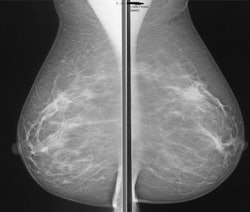

Kuhl and colleagues investigated whether a streamlined protocol, consisting only of the first postcontrast subtracted images and their maximum intensity projection (MIP) reconstructions, would be suitable for screening purposes. The idea was to trade some of the high sensitivity of breast MRI for acquisition and interpretation speed, with a long-term goal of increasing access to breast MRI by reducing the cost associated with the examination, according to Kuhl.

Kuhl and colleagues tested the protocol in a population of 443 women at increased risk of breast cancer who had undergone 606 breast MRI screening studies. Images were read by experienced breast radiologists who were asked to first review the MIPs and search for significant enhancement, and then to evaluate the first postcontrast subtracted images for any further categorization. (The first postcontrast subtracted images show the change in image due to contrast; MIP is a volume rendering method for 3D data.)

After the radiologists had read images produced with the streamlined protocol, they then analyzed the full diagnostic breast MRI protocol. Kuhl's group then compared the diagnostic yield and accuracy of the streamlined readings versus that of the full protocol.

Kuhl's team found that the average time required to read MIPs was 2.8 seconds, while 28 seconds were required for the postcontrast subtracted images. Patient setup consumed the rest of the time required for the three-minute protocol. A total of 11 breast cancers were diagnosed, for an additional yield of 18.2 cancers per 1,000 women.

Of these cancers, four were ductal carcinoma in situ (DCIS) and seven were invasive, with a median size of 8 mm. All were intermediate or high grade. The streamlined protocol detected nine (82%) of the 11 cancers; specificity of the protocol was the same as that of the full protocol, at 94.4%. The streamlined protocol had 33 false-positive diagnoses, versus 35 for the full procedure.

The negative predictive value of the streamlined protocol was 99.6%, compared with 99.8% for the full protocol, according to the researchers.